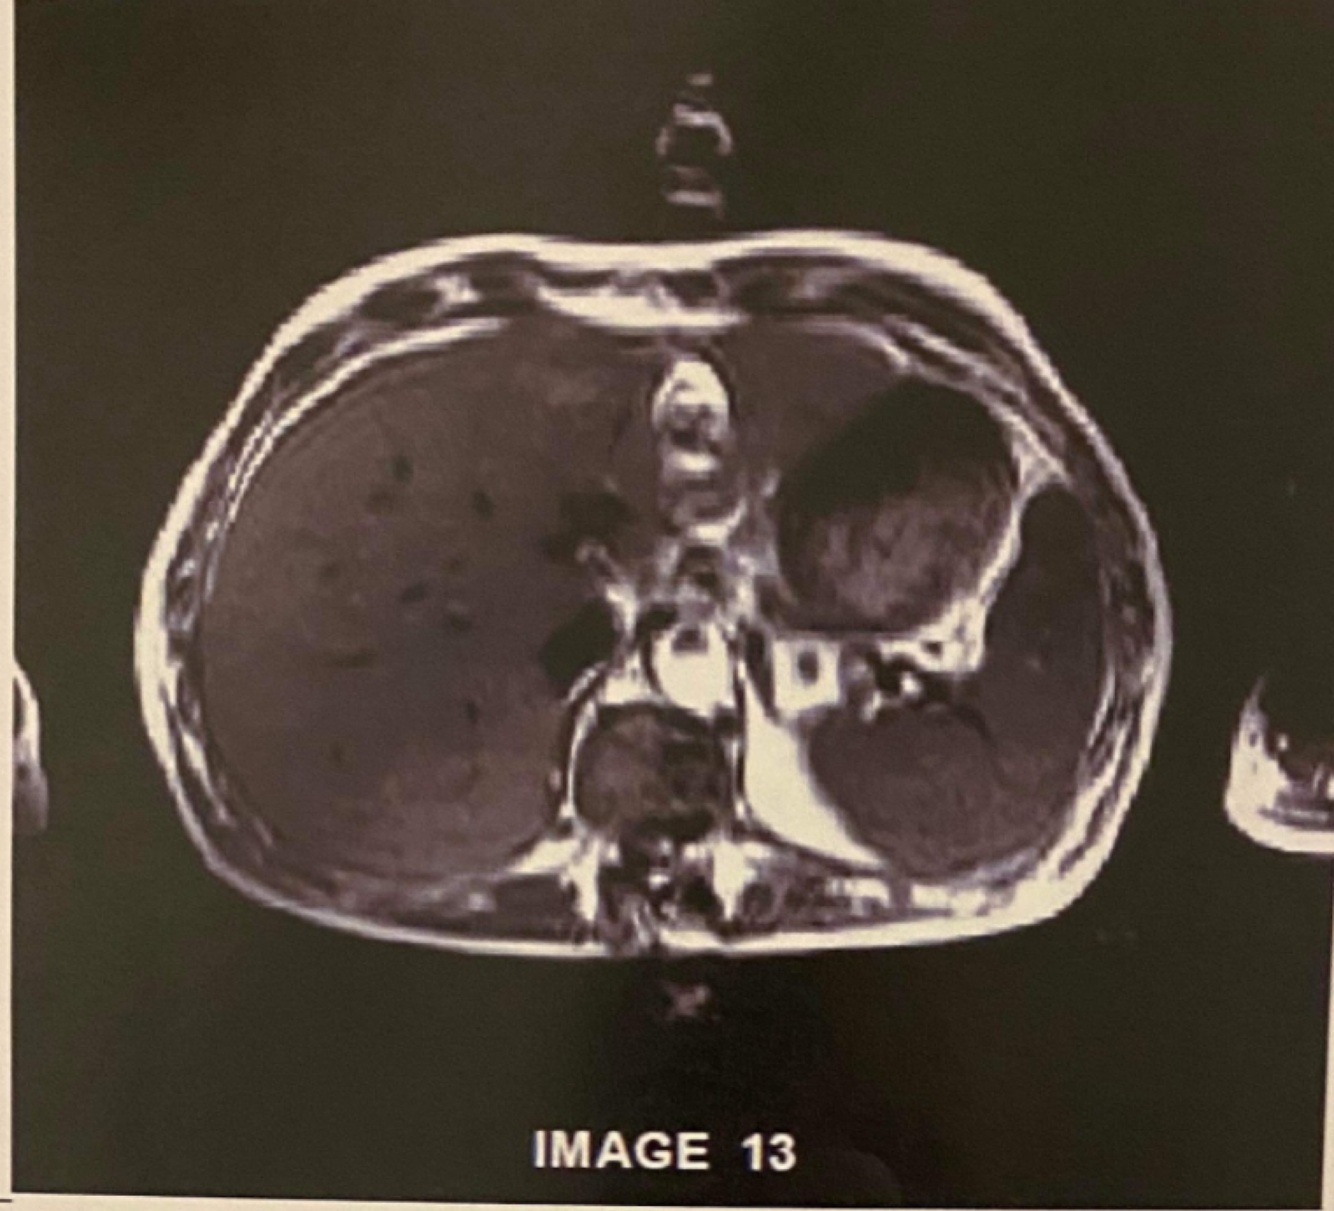

What is the artefact in this image caused by?

Metallic implant

Use FSE to try and reduce artefacts from metal implants